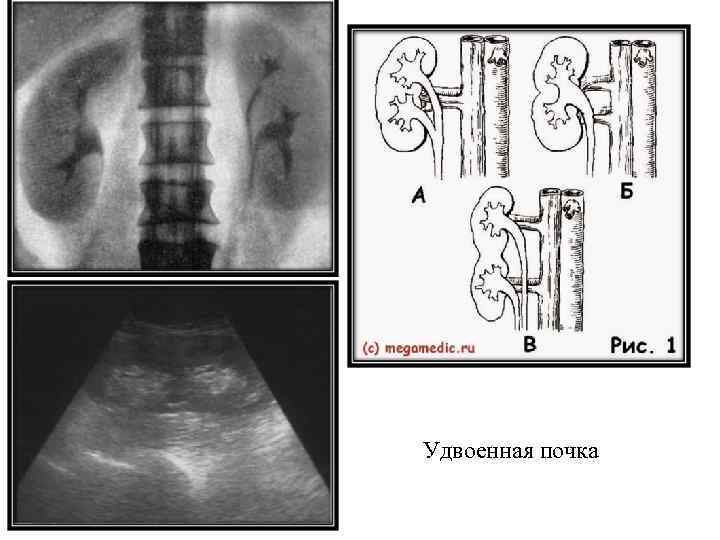

Удвоенная почка

Удвоенная почка